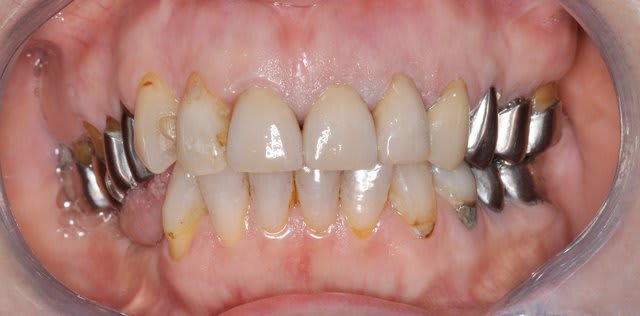

Voilà un exemple, fait à f/22, 320ISO, 1/60sec, 85mm Nikkor, j'ai juste croppé l'image.

Sur la photo il faut regarder 11/21/22, ne pas s'arrêter sur les restaurations de quelques collets, qui ont été refaits, évidemment.